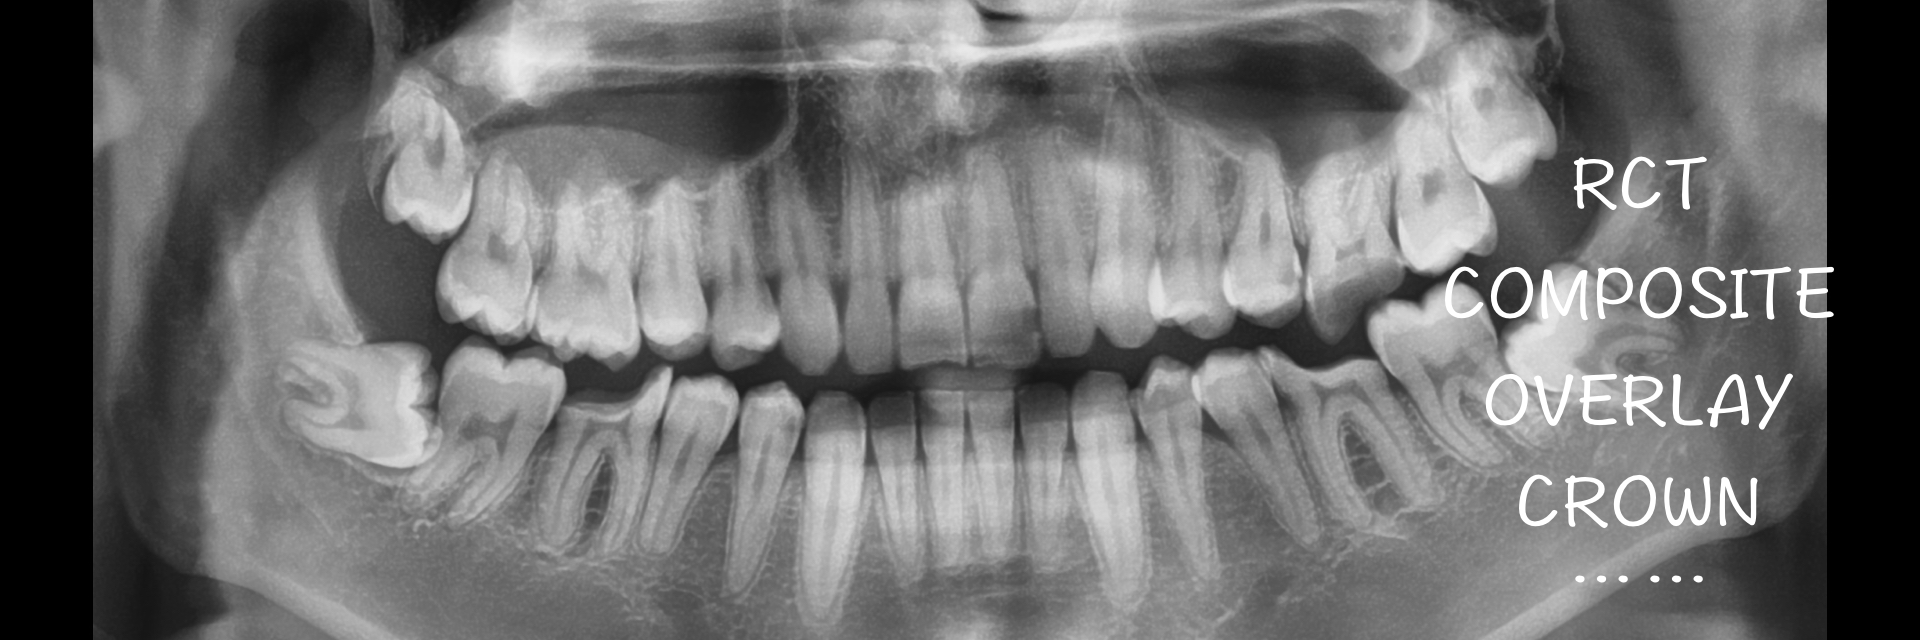

嵌体|E.Max .16.36.46

温州佳洁口腔 朱照鸿 医生 | 技师:尹群